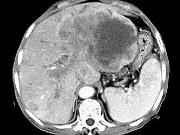

问题 女,73岁,中上腹痛1月余,患者黄疸、消瘦,CT检查如下图,最可能的诊断是()

选项 A.肝脓肿 B.巨块型肝癌 C.肝血管瘤 D.肝淋巴管瘤 E.肝胆管细胞癌

答案 B